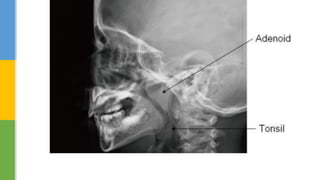

the typical pediatricOSA patient was one with adenotonsillar hypertrophy

 Most children with obstructive sleep apnea are aged 2-10 years

(coinciding with adenotonsillar lymphatic tissue growth).

 Adenotonsillar hypertrophy